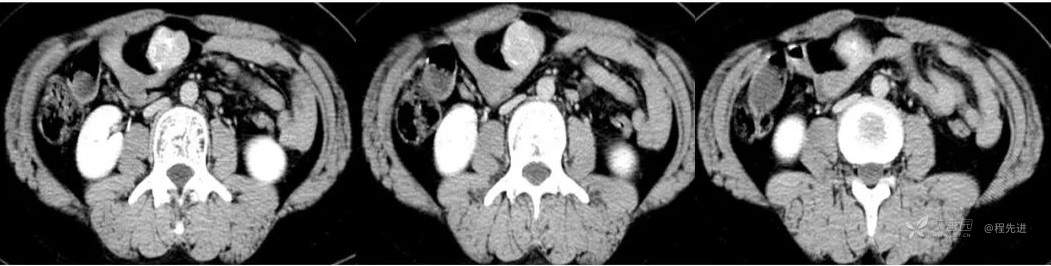

CT

图像依次为平扫(CT值46HU),动脉期(CT值138HU),静脉期(CT值137HU),延时期(CT值96HU)斜矢状位重建